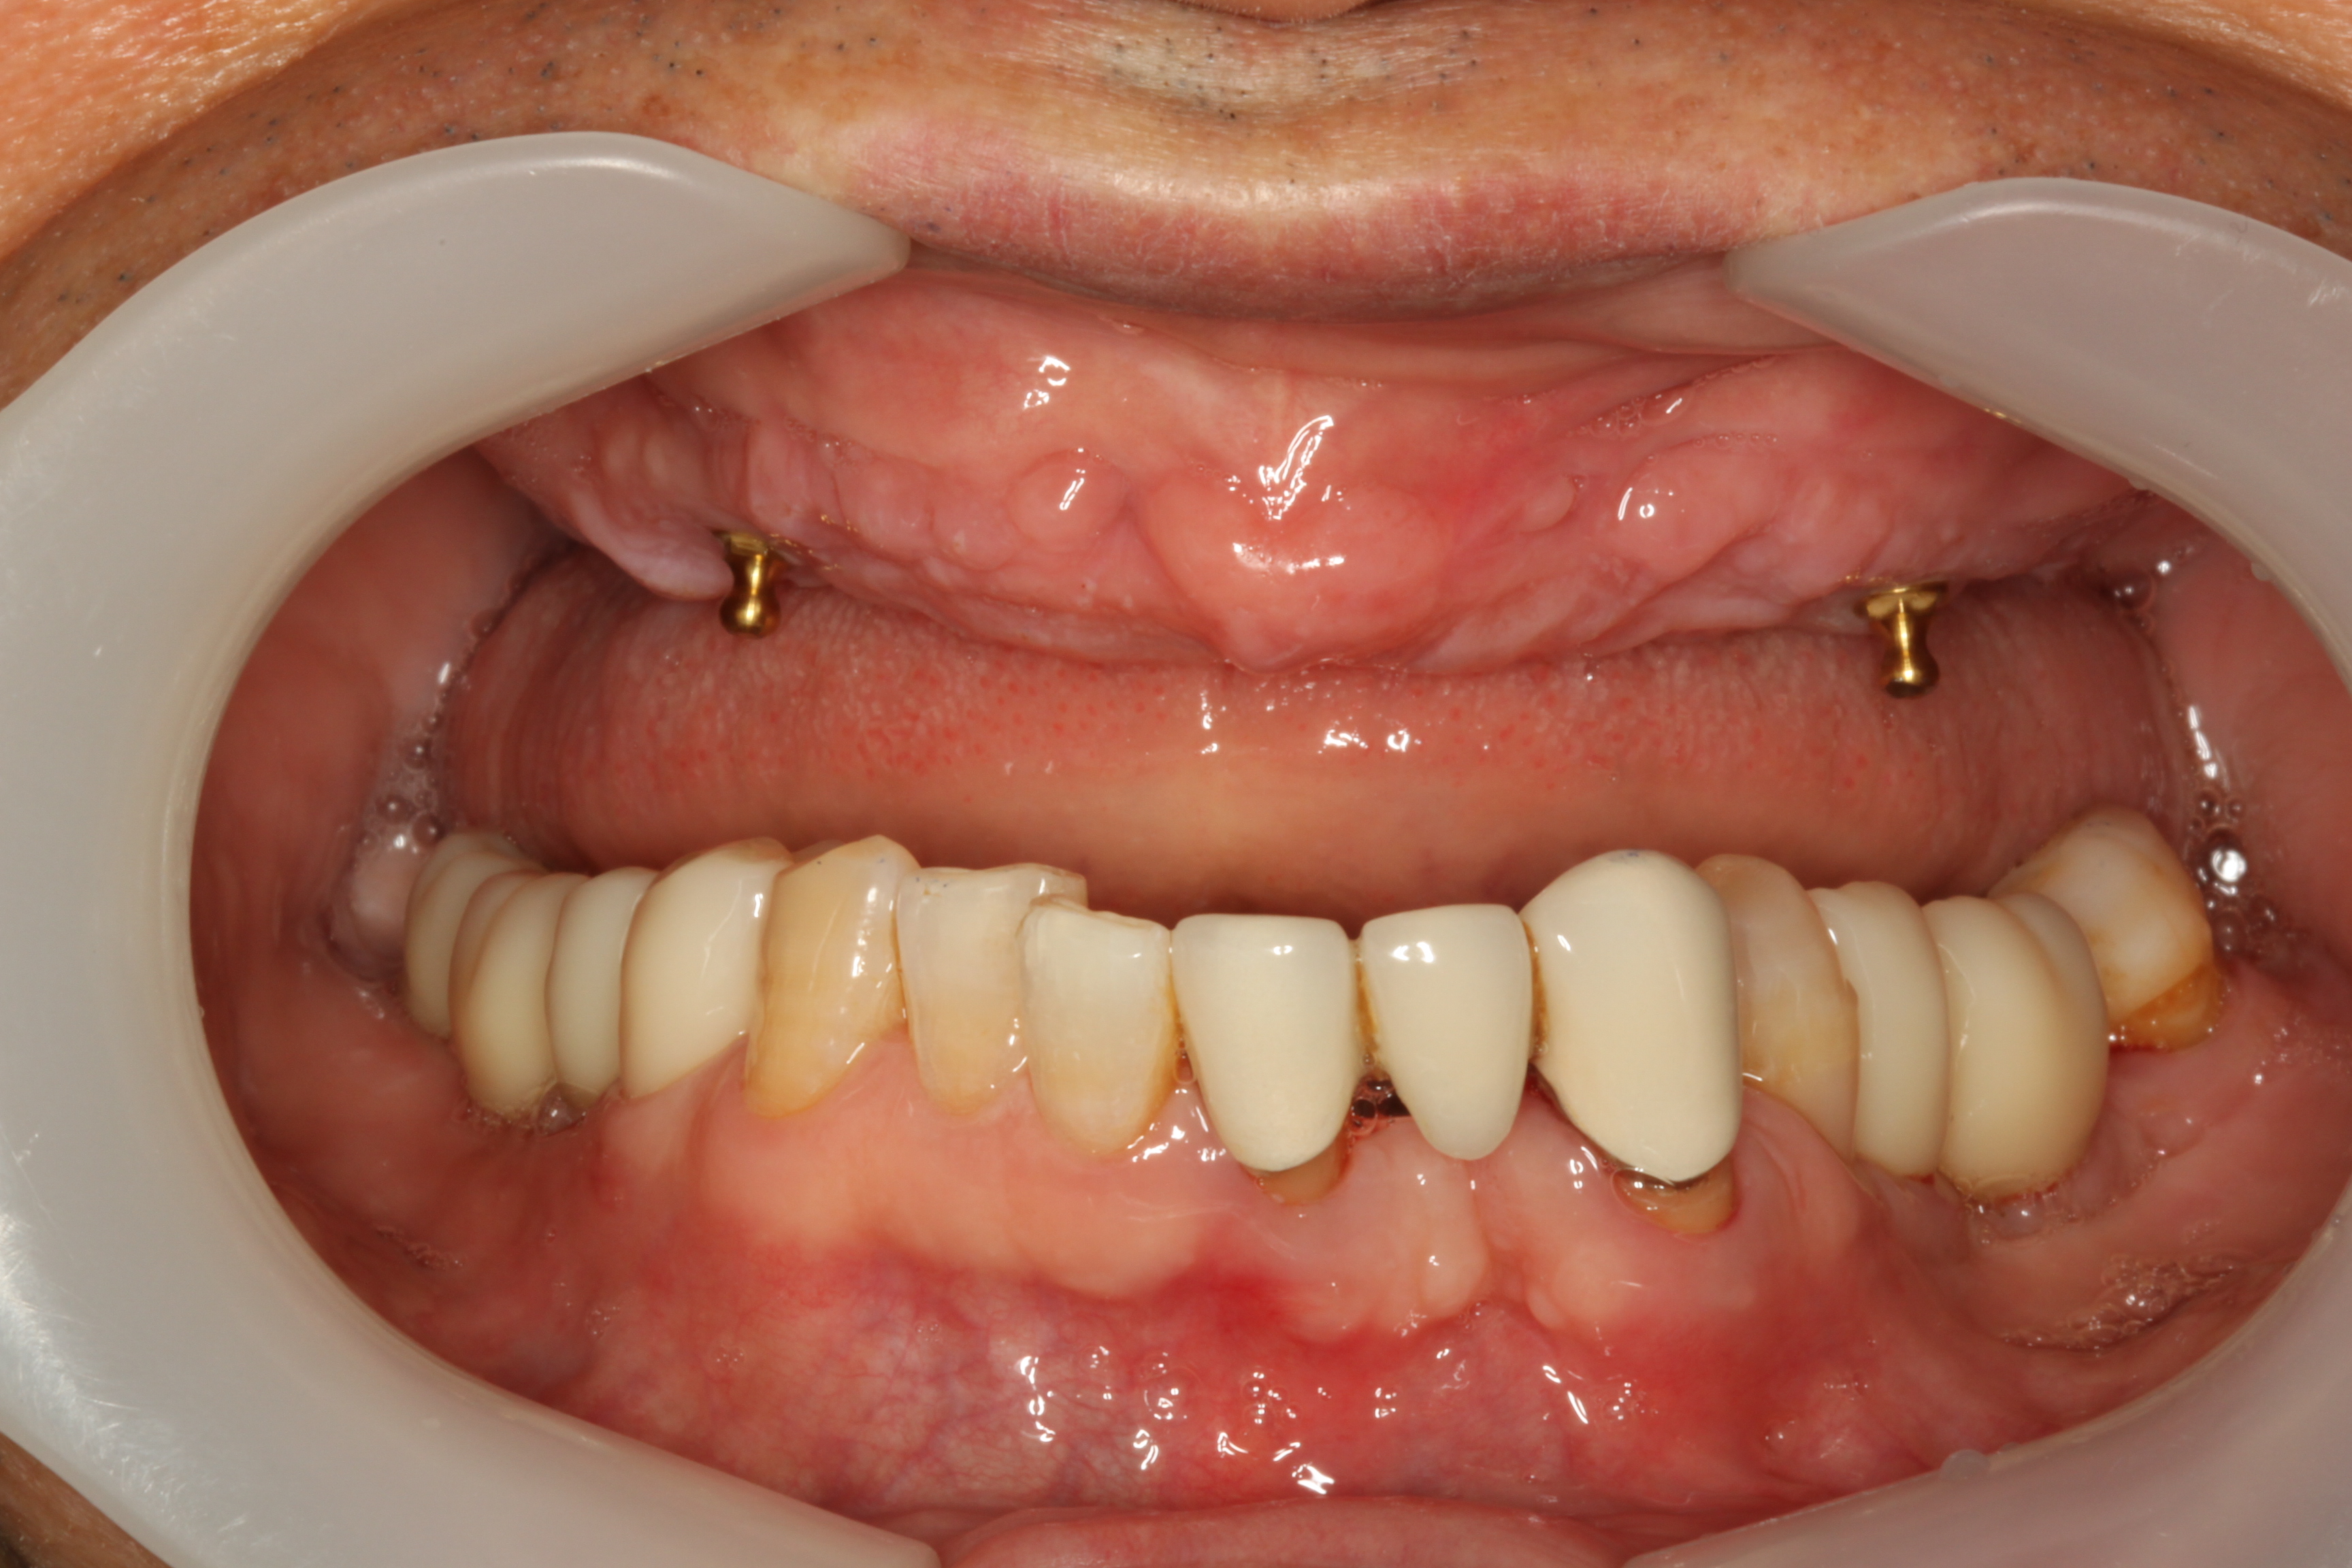

BEFOREAFTERBEFOREAFTER(식립)AFTER(착용)

임플란트 틀니